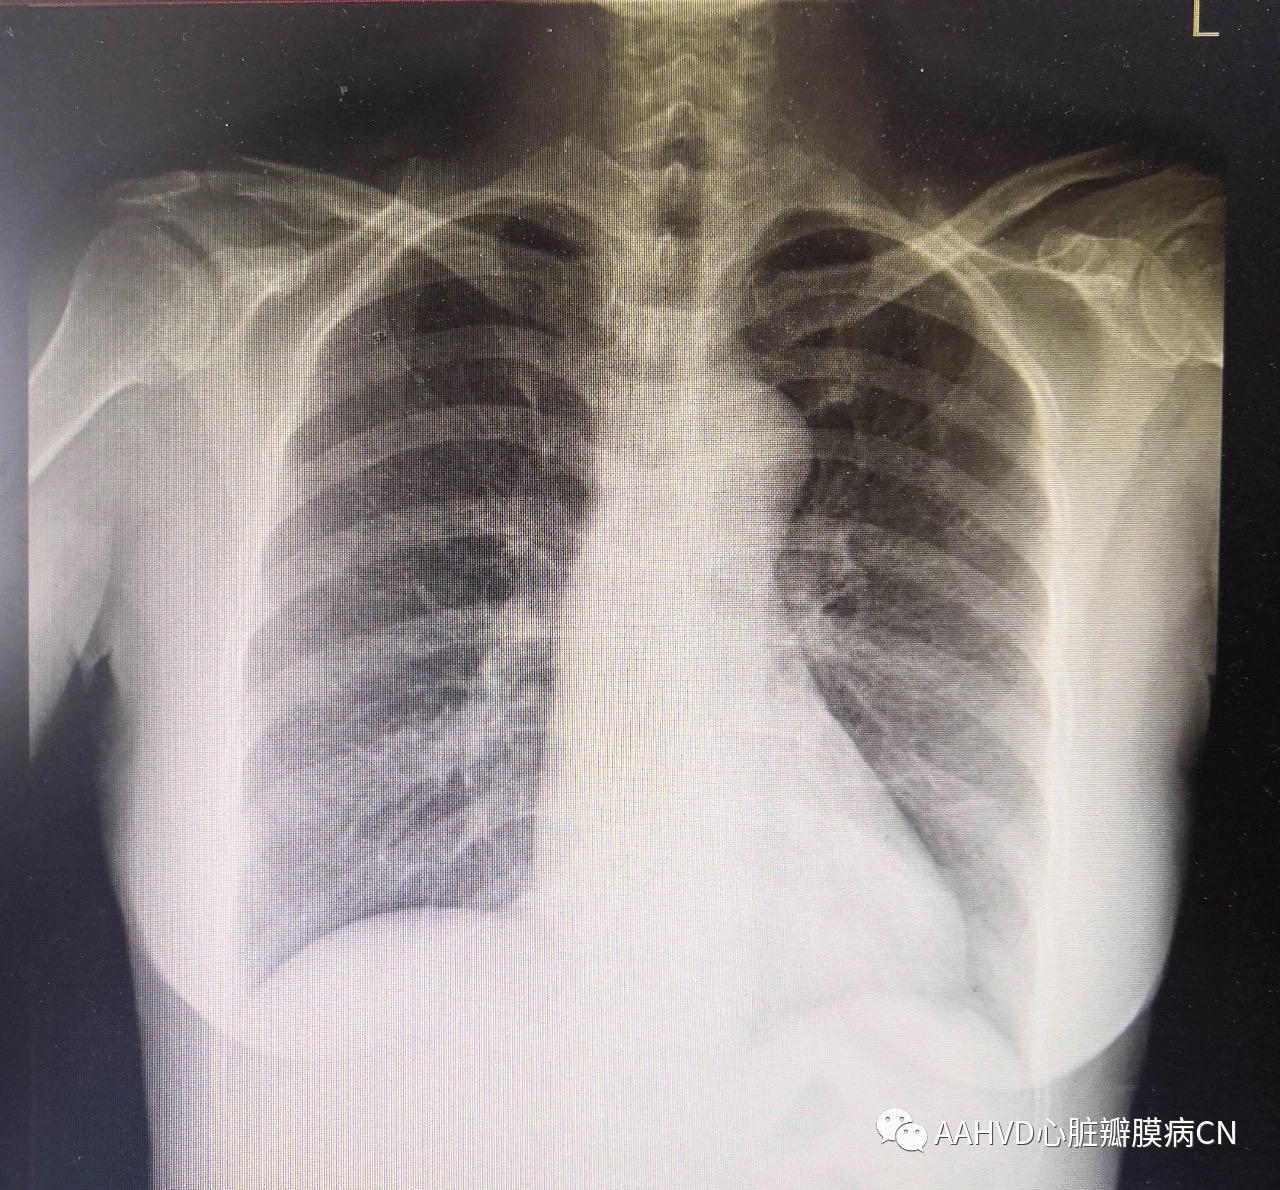

女性,52岁,主诉:心慌憋气1月余

术前胸片